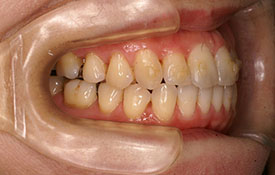

インビザラインの治療例:CASE-1

| プロフィール | 42歳 女性 |

|---|---|

| 所見 | 他院で行われた矯正歯科治療後の後戻りに悩まれて来院されました。 アイライナーの装着は、1日平均20時間ほどでした。 |